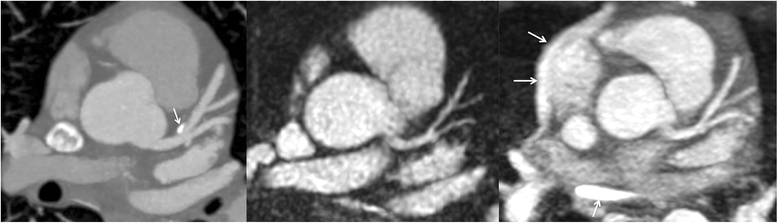

Background: Coronary magnetic resonance angiography (MRA) is usually obtained with a free-breathing navigator-gated 3D acquisition. Our aim was to develop an alternative breath-hold approach that would allow the coronary arteries to be evaluated in a much shorter time and without risk of degradation by respiratory motion artifacts. For this purpose, we implemented a breath-hold, non-contrast-enhanced, quiescent-interval slice-selective (QISS) 2D technique. Sequence performance was compared at 1.5 and 3 Tesla using both radial and Cartesian k-space trajectories.

Methods: The left coronary circulation was imaged in six healthy subjects and two patients with coronary artery disease. Breath-hold QISS was compared with T2-prepared 2D balanced steady-state free-precession (bSSFP) and free-breathing, navigator-gated 3D bSSFP.

Results: Approximately 10 2.1-mm thick slices were acquired in a single ~20-s breath-hold using two-shot QISS. QISS contrast-to-noise ratio (CNR) was 1.5-fold higher at 3 Tesla than at 1.5 Tesla. Cartesian QISS provided the best coronary-to-myocardium CNR, whereas radial QISS provided the sharpest coronary images. QISS image quality exceeded that of free-breathing 3D coronary MRA with few artifacts at either field strength. Compared with T2-prepared 2D bSSFP, multi-slice capability was not restricted by the specific absorption rate at 3 Tesla and pericardial fluid signal was better suppressed. In addition to depicting the coronary arteries, QISS could image intra-cardiac structures, pericardium, and the aortic root in arbitrary slice orientations.

Conclusions: Breath-hold QISS is a simple, versatile, and time-efficient method for coronary MRA that provides excellent image quality at both 1.5 and 3 Tesla. Image quality exceeded that of free-breathing, navigator-gated 3D MRA in a much shorter scan time. QISS also allowed rapid multi-slice bright-blood, diastolic phase imaging of the heart, which may have complementary value to multi-phase cine imaging. We conclude that, with further clinical validation, QISS might provide an efficient alternative to commonly used free-breathing coronary MRA techniques.